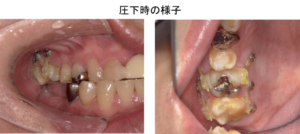

矯正的圧下は模型上でシミュレーションを行ってから行いました。圧下の経過を示します。

治療中

矯正用のアンカースクリューを用いて右上の奥歯を圧下しました。

右上の奥歯を圧下した後の口腔内写真です。